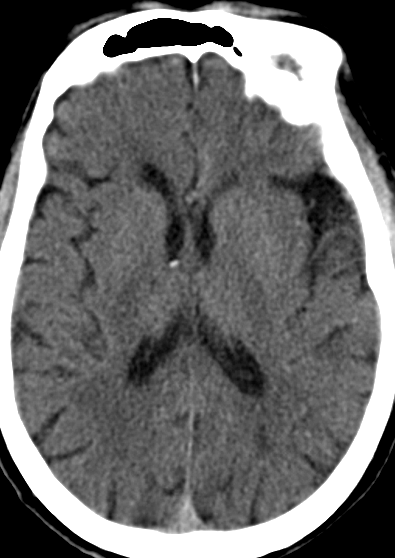

现病史:2022年9月26日突发眩晕,视物旋转,伴恶心、呕吐、言语不清、饮水呛咳、排尿困难、行走不稳,7小时后被送至当地医院完善头颅CT平扫未见脑出血,诊断为“急性脑梗死”予抗血小板聚集、稳定斑块等治疗。3天后完善头颅MRI+MRA显示“1.脑干、双侧小脑半球、双侧枕叶、双侧丘脑多发急性脑梗塞2.基底动脉、左侧大脑后动脉P2段狭窄,左侧颈内动脉起始段局部重度狭窄”。治疗后症状有改善。2022-10-8转入我科。

2022-09-29外院头颅MRI+MRA:

1. 脑干、双侧小脑半球、双侧枕叶、双侧丘脑多发急性/亚急性脑梗塞

2. 基底动脉、左侧大脑后动脉P2段局部狭窄,左侧颈内动脉起始段局部重度狭窄,左侧颈内动脉C3段、右侧颈内动脉虹吸部及右侧椎动脉颅内段局部狭窄。

我院头颈CT/CTA:

右侧锁骨下动脉迂曲明显,左侧颈总动脉迂曲,左颈内动脉重度狭窄